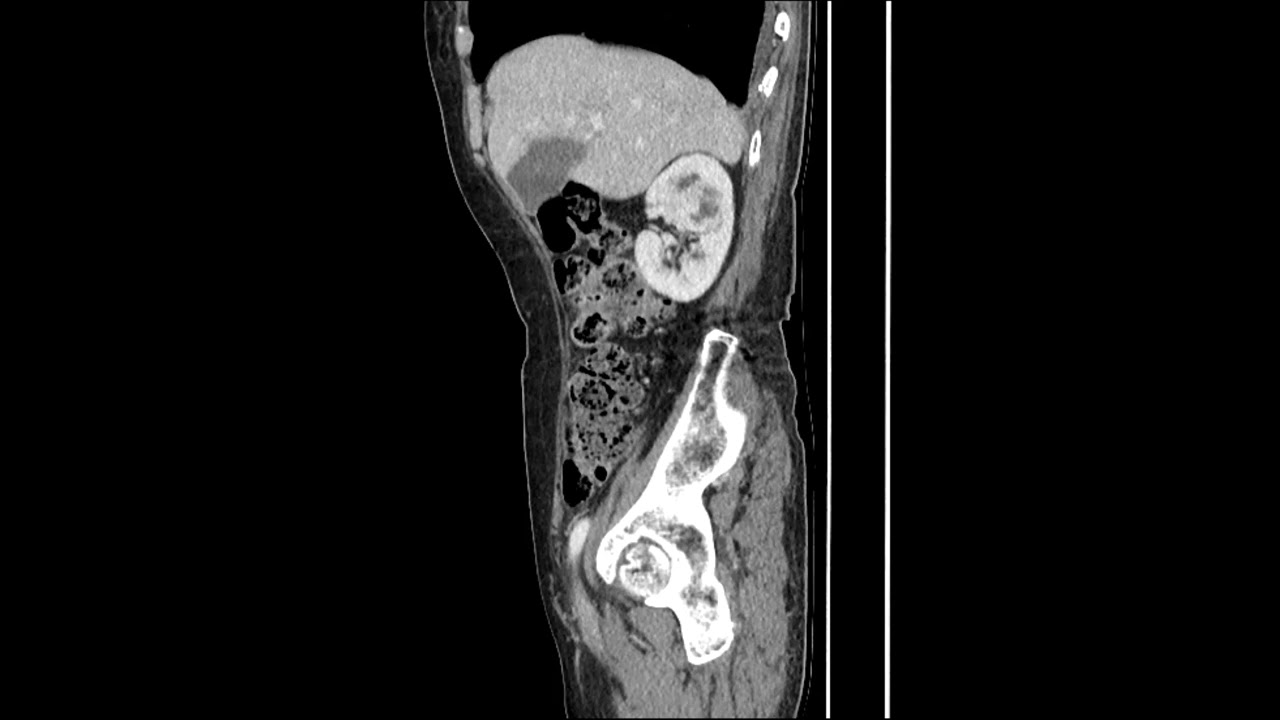

Скачать или смотреть RCC(renal cell carcinoma)

RCC(renal cell carcinoma)

ABDOMEN PELVIS CECT;

Clinical Information:

. 4.6cm well defined Rt renal enhancing tumor

-- probable RCC (REC. BX)

. another two subcentimeter sized both renal cortical cysts

. two hepatic cyst in seg4,7

. 2.1cm enhancing hepatic nodule in seg6/7

-- DDx. hepatic hemangioma

. small amount of pelvic fluid collection